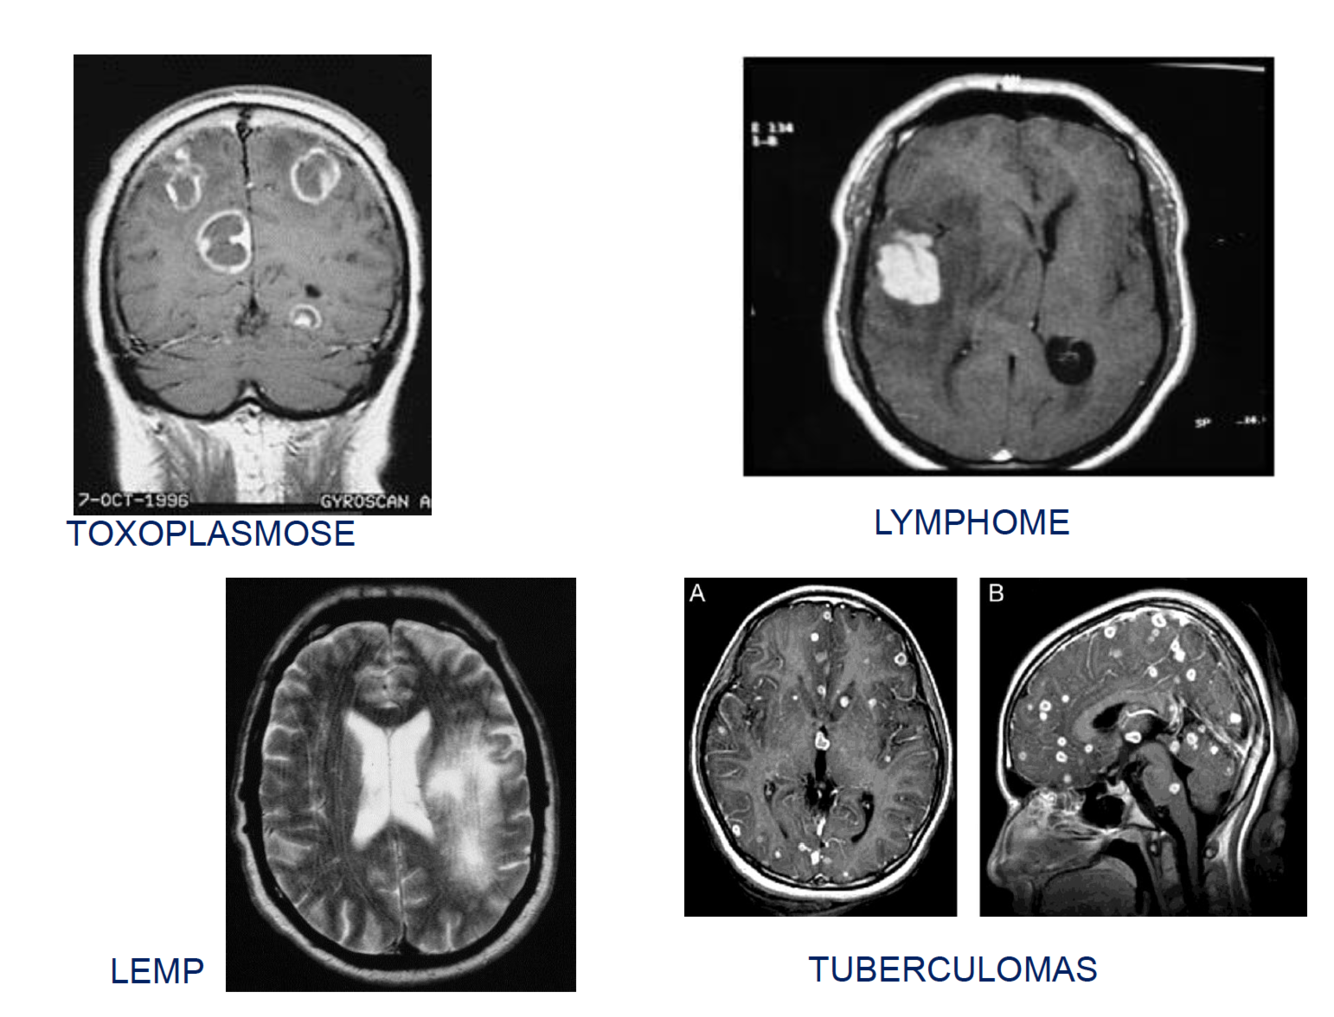

SIDAの症状(tuberculose, herpès, pneumocytose, Kaposi, CMV, LEMP, Lymphome)が出現する際のCD4の数値はどれほどか?